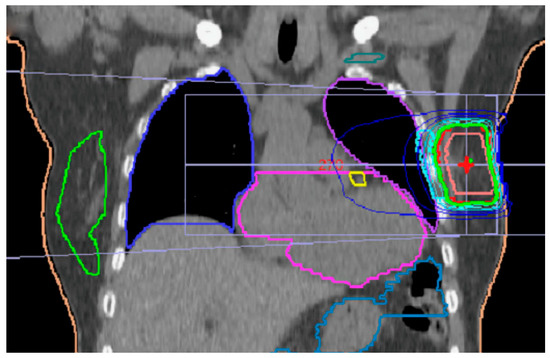

2. Materials and Methods

3.1. Quantitative Dose-Volume Analysis of PTV

3.2. Organs at Risk